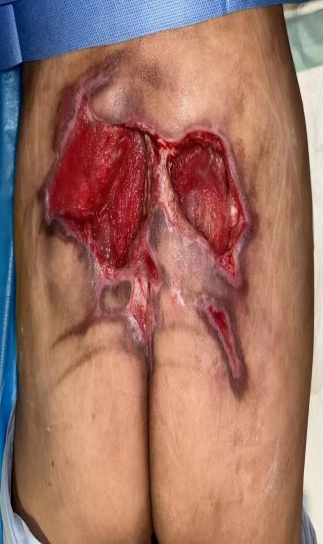

壓力性損傷(壓瘡)的特色治療—Masquelet技術+NPWT+PRP+各種穿支皮瓣技術

壓力性損傷(壓瘡)的特色治療—肌皮瓣技術+NPWT